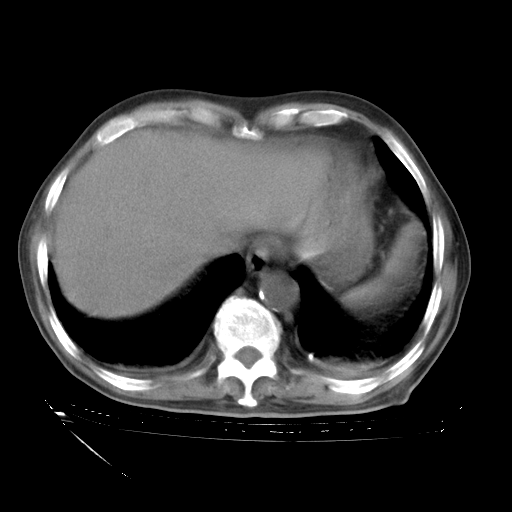

甲强龙80mg/日+抗结核治疗(异烟肼+利福霉素+乙胺丁醇)10天。复查肺部CT。

治疗10天肺部CT

补充下:5月9日胸部CT:似乎已见双下肺胸腔积液了,鉴于目前有下肢水肿,肝功示:白蛋白低,应注意多浆膜腔积液(漏出液可能大?),需注意!